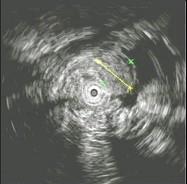

问题 男性,60岁。胃溃疡病史8年,近3月腹痛、腹胀、食欲减退、消瘦明显、粪隐血持续阳性,应用抗酸剂治疗胃痛无效。胃镜检查如图:该病人最可能的诊断是 ( )

选项 A、胃泌素瘤 B、胃溃疡恶变 C、穿透性胃溃疡 D、顽固性溃疡 E、复合溃疡

答案 B